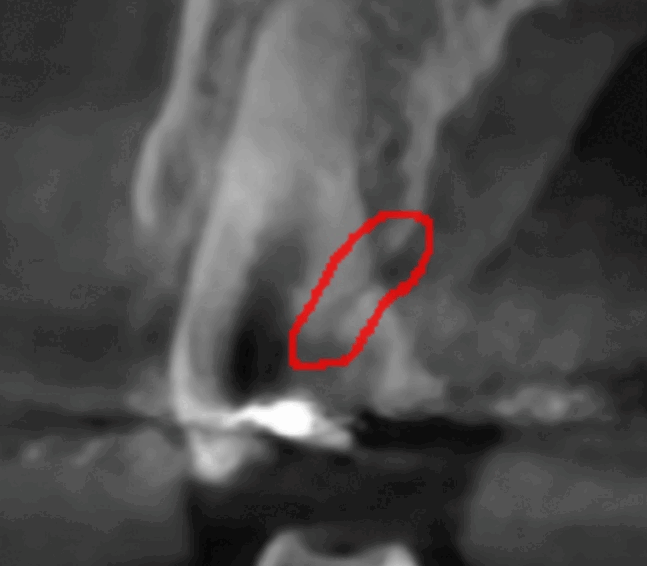

특히 치아 금이 간 경우는 육안으로 확인하기 어려운데

증상에 의존하기보다는

ct 장비 등을 활용해 정확히 확인해보는게 좋습니다.

ct로 금이 간 부분을 발견했어요!

육안으로 보기 힘든 부분까지 정밀하게 확인이 가능하여

원인 부분만 치료할 가능성이 높아집니다.